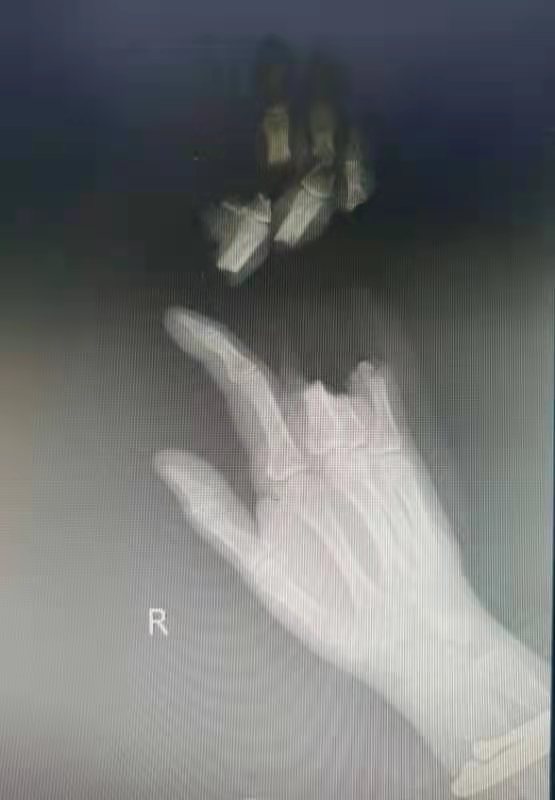

经接诊的主治医生邓淑华发现,文女士右手第3、4、5指已经完全断离,并且被切成了很多段,并有挫伤,再植难度大,但文女士强烈要求再植,值得欣慰的是,她的家人将断指全部用干净纸巾包裹好,断指受到了较好的保护。

邓淑华医生立即安排急诊手术,为文女士实施右第3、4、5指离断伤清创、再植术。紧张的手术整整耗时了九个多小时,经过手术团队的精密配合,在显微镜下给文女士右手中指、无名指、小指的动脉吻合了十一处,单中指就缝合了六处动脉、四根静脉,但值得高兴的是断指再植很成功,残端修整也比较完美,目前文女士再植的无名指、小指存活良好,中指远端部分坏死,后期还需要观察,并做好功能康复训练。